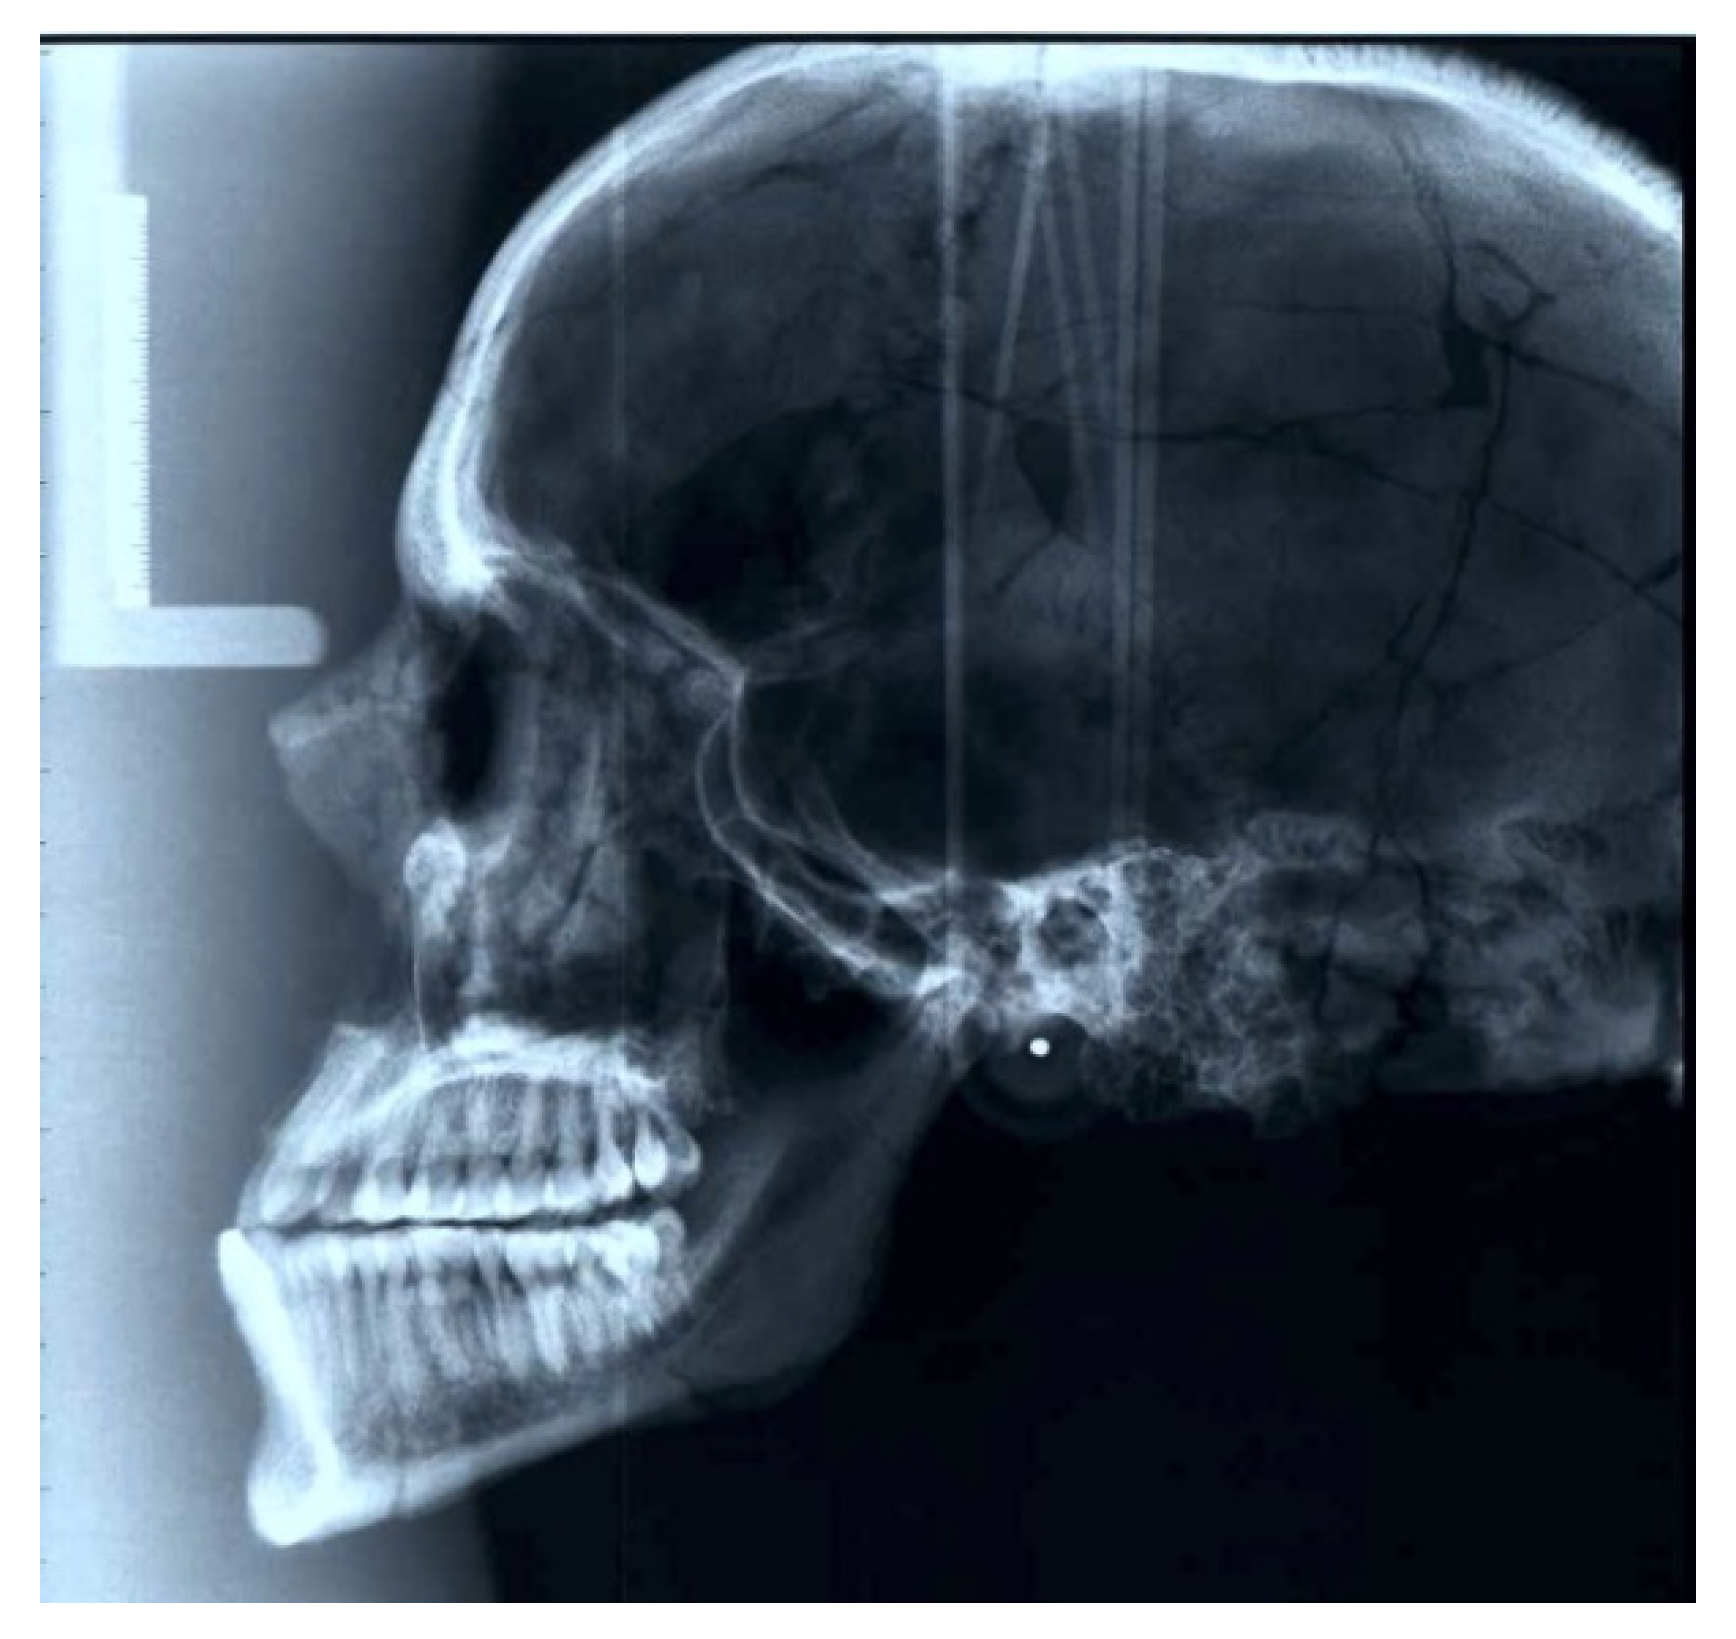

3.4. Dental Pathology

3.5. 3D Modeling